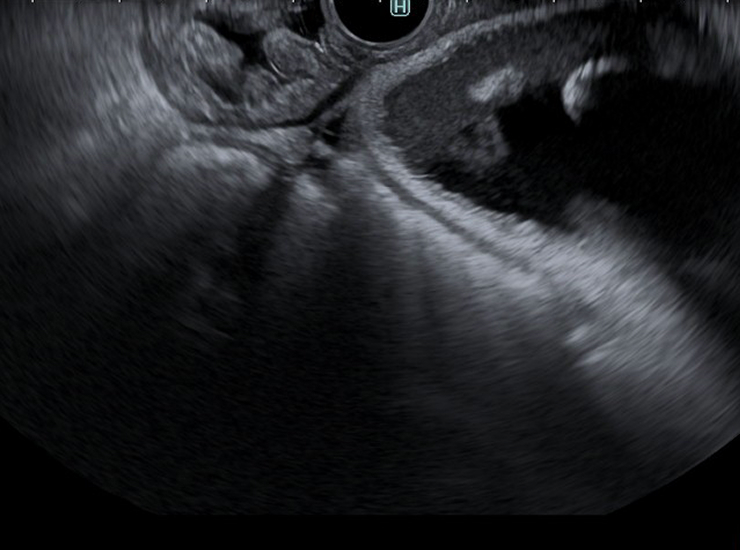

Endoscopic ultrasound (EUS) combines ultrasound and conventional endoscopy technologies to see beyond the walls of the gastrointestinal tract. EUS allows endoscopists to visualize all five layers of the GI tract, as well as surrounding tissue and organs.

The diagnostic radial array echoendoscope provides a 360°, cross-sectional view of the GI tract and is primarily used for screening. The curvilinear echoendoscopes are useful for therapeutic applications such as tissue sample collection, cyst drainage, biopsies of lesions/lymph nodes and injection for pain management.

Curved linear array echoendoscope used for therapeutic applications such as tissue sample collection, cyst drainage, biopsies of lesions/lymph nodes and injection for pain management. The GF-UCT180’s ultrasound transducer has a broad bandwidth and high sensitivity, offering ultrasound imaging with high resolution and penetration and less noise when operating in B-mode.4

Diagnostic radial array echoendoscope used to assess anatomy of the GI tract and surrounding structures. It provides a 360° cross-sectional view of the GI tract and is primarily used for screening.